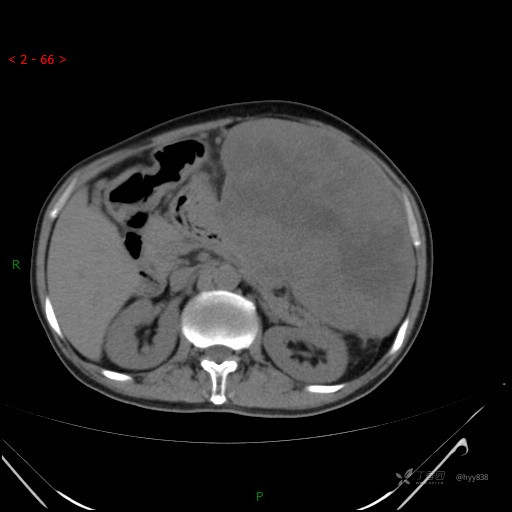

增强动脉期